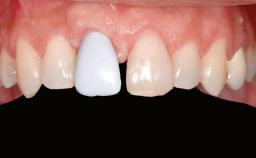

A 46-year-old woman was referred for treatment whose main complaints were mobility of her fixed partial dentures (right maxilla and left mandible) and periodontal bleeding during function. She also reported having taken systemic antibiotics to treat recurrent swelling in the area of the upper left molars. The patient had not seen a dentist for at least 2 years. She did not smoke and had no history of major systemic disease other than two minor orthopedic procedures some years back. The first-visit examination revealed poor plaque control, tooth mobility, periodontal disease, and a residual dentition widely associated with deep periodontal pockets.

Prosthesis Type FDP

Lip Line No exposure of papillae Exposure of papillae Full exposure of mucosa margin

Periodontal Phenotype Low-scalloped, thick Medium-scalloped, medium-thick High-scalloped, thin